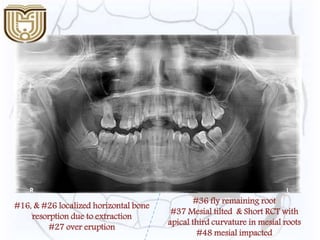

#16, & #26 localized horizontal bone

resorption due to extraction

#27 over eruption

#36 fly remaining root

#37 Mesial tilted & Short RCT with

apical third curvature in mesial roots

#48 mesial impacted